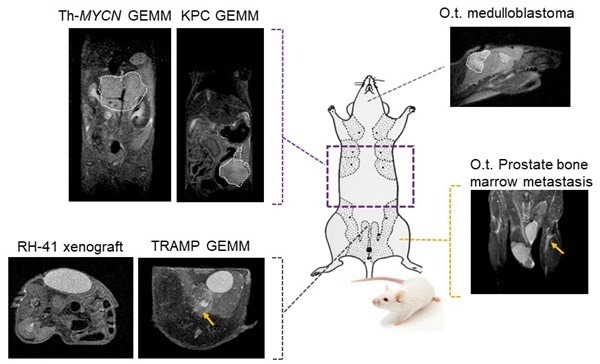

Tumor visualization in various cancer models: Fat-suppressed T2-weighted imaging can be used to detect and quantitatively characterize the growth of a wide range of cancer models. Image Credit: Scintica Instrumentation Inc

The M-Series devices are suitable for studying various tumor types and disease phases. Since no alteration of tumor cells is necessary, models such as xenografts, orthotopic, transgenic, and patient-derived xenografts can be studied in a wide range of imaging subjects to focus on.

Fat-suppressed T2-weighted imaging can be used to detect and quantitatively characterize the growth of a wide range of cancer models. Image Credit: Scintica Instrumentation Inc

MRI is a complementary method to bioluminescence imaging in the detection of tumors, allowing a more precise assessment of the location and extent of orthotopic tumors (here, an orthotopic model of prostate bone marrow metastasis). Image Credit: Scintica Instrumentation Inc